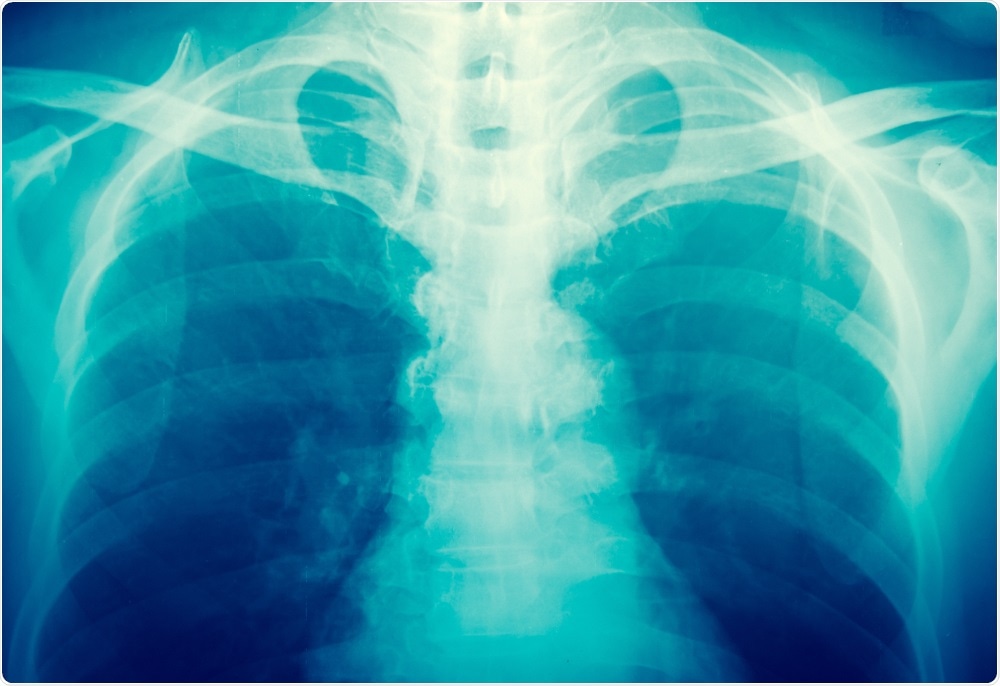

X-ray image - taken by toeytoey

toeytoey | Shutterstock